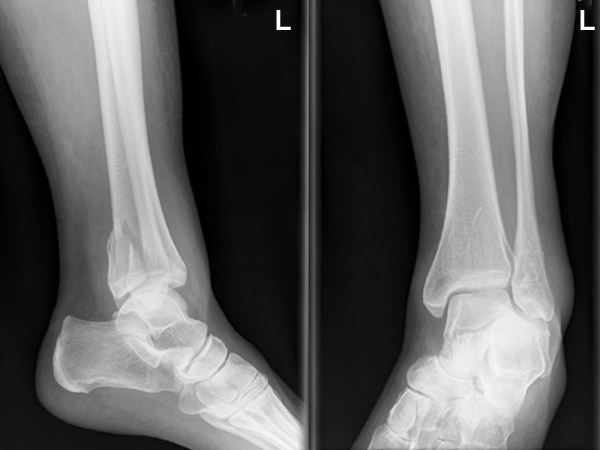

Hat doch was, so ein Knöchel ... hier geht die Bruch-Geschichte weiter